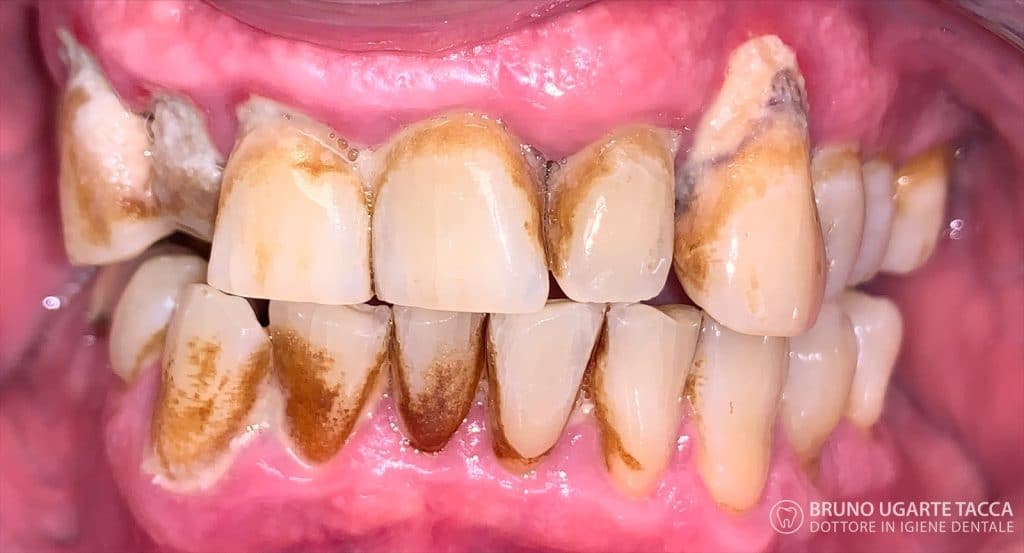

Performing the complete instrumentation

supragingival and subgingival with ultrasonic and / or manual instruments in one

single session or in two sessions at most performed over 2 days